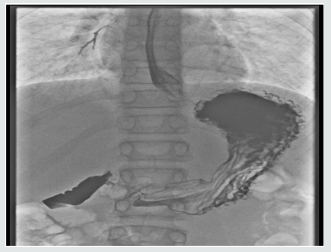

The rest of her systemic review was normal. She was able to eat and drink “normally” but bedside swallow was not formally assessed. She was treated for a respiratory tract infection with intravenous antibiotics and regular salbutamol nebulisers. A few hours later, she developed increased shortness of breath and a peri-arrest call was made. However, examination findings were unchanged, her management remained the same. Her bloods results were Hb 133, WBC 8.9, Plt 293, CRP 5, U&E NAD, LFT NAD. The CXR was reported as left lower lobe atelectasis with an increase of the peribronchial and perivascular interstitial infiltrates (Figure 1). she was reviewed by a second Paediatric Consultant in the ward later, who felt this was more likely to be an upper airway obstruction. He stopped the salbutamol nebulisers, continued the Atrovent nebulisers, started prednisolone and advised to suction intermittently, request an ENT review and arrange a neck X-ray and barium swallow. Neck X-ray was normal (Figure 1). An ENT Consultant reviewed the following day with flexible nasendoscopy which revealed a normal larynx, good vocal cord movement and very slight inflammation on the right arytenoid. The nasendoscopy findings were noted to be insufficient to explain the symptoms. The ENT impression was laryngopharyngeal reflux. She was put on Gaviscon Advance after food and before bedtime. she gradually improved over next three days. She was discharged home on Gaviscon Advance. Barium swallow, done a month later, was reported ‘the mid and distal oesophagus giving a shaggy appearance most likely due to Oesophageal Candidiasis’ (Figure 2).